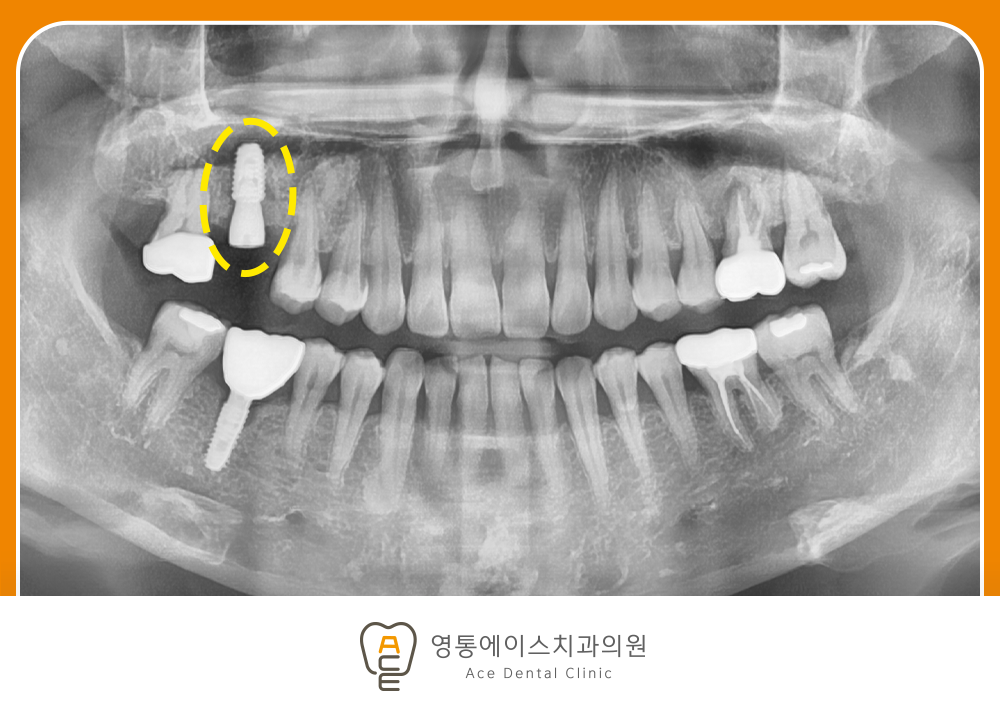

오늘 함께 살펴볼 케이스는 위 사진과 같이 위쪽 어금니 하나를 천천히 볼 텐데요. 주황색 화살표가 가리키는 부위를 자세히 봐주시기를 바랍니다. 치아 주변으로 방사선 상 까맣게 감싸고 있는 것을 확인하실 수 있습니다. 다른 치아들의 경우에는 까만 부분이 보이지 않는 데에 반해 무언가 상태가 좋지 않음을 아실 수 있습니다. 😭

조금 더 자세하게 말씀드리자면, 어금니 뿌리 주변으로 염증이 다량 발생해 있는 모습이라고 말씀드릴 수 있습니다. 염증은 기본적으로 뼈를 파괴시켜 소실시키게 만드는 역할을 하고 있습니다. 이 정도로 진행이 되었다면 자연치 보존은 더욱이 어려워지는 편입니다.

그리고 문제점을 하나 더 발견할 수 있습니다. 앞서 다른 케이스들에서도 종종 보이는 경우인데요. 어금니가 정출되어 아래쪽으로 솟구치고 있는 모습임을 알 수 있습니다. 단순히 교합관계와 형태로만 이야기할 수 없습니다.

그 이유는 유독 해당 어금니가 정출되어 교합이 높기 때문에 저작 운동을 할 때 맞은편 치아와 계속 맞닿기 때문입니다. 심지어 해당 치아는 신경치료가 되어 있지 않아 그대로 자극과 통증이 전달될 수밖에 없습니다.

이와 같은 두 가지 이유로 인해 해당 어금니는 발치 후 임플란트를 진행하기로 했습니다. 🦷👍

임플란트 식립 후 모습입니다. 컴퓨터 분석을 활용한 방식으로 진행하여 가장 이상적인 위치에 잘 식립이 되었는데요. 더욱이 이번 케이스와 같이 위쪽 어금니 부위의 경우에는 상악동이라고 불리는 해부학적 구조물을 조심하며 식립해야 합니다.

자칫하면 상악동이 뚫려버리는 상악동 천공이 발생할 수도 있으며, 이 거리가 충분하지 않다면 상악동 거상술을 부가적으로 수술해야 하기 때문입니다. 그렇기 때문에 주변의 상태도 함께 꼼꼼하게 파악해야 좋은 예후를 기대할 수 있습니다. 😁

임플란트 전과 후의 모습을 비교해 보았습니다. 아직은 식립 후 잇몸뼈와 결합이 잘 이루어질 수 있도록 기다리고 있으나, 머지않아 본뜨기 작업을 통해 보철물을 제작하여 연결해 드릴 예정입니다.